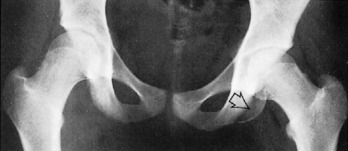

The posterior margin of the acetabulum, somewhat obscured by the femoral head and requiring an oblique view to see adequately, may arise from a separate ossification center and easily simulate a fracture because of its linear appearance. This variation is often a bilateral finding. A variable-sized ununited center, the os acetabuli, may persist throughout life. It is located along the superolateral margin of the acetabulum (Fig. 16-45).

Fig. 16-45 Os acetabuli. The right side demonstrates this normal variant (arrow). None is seen on the left.